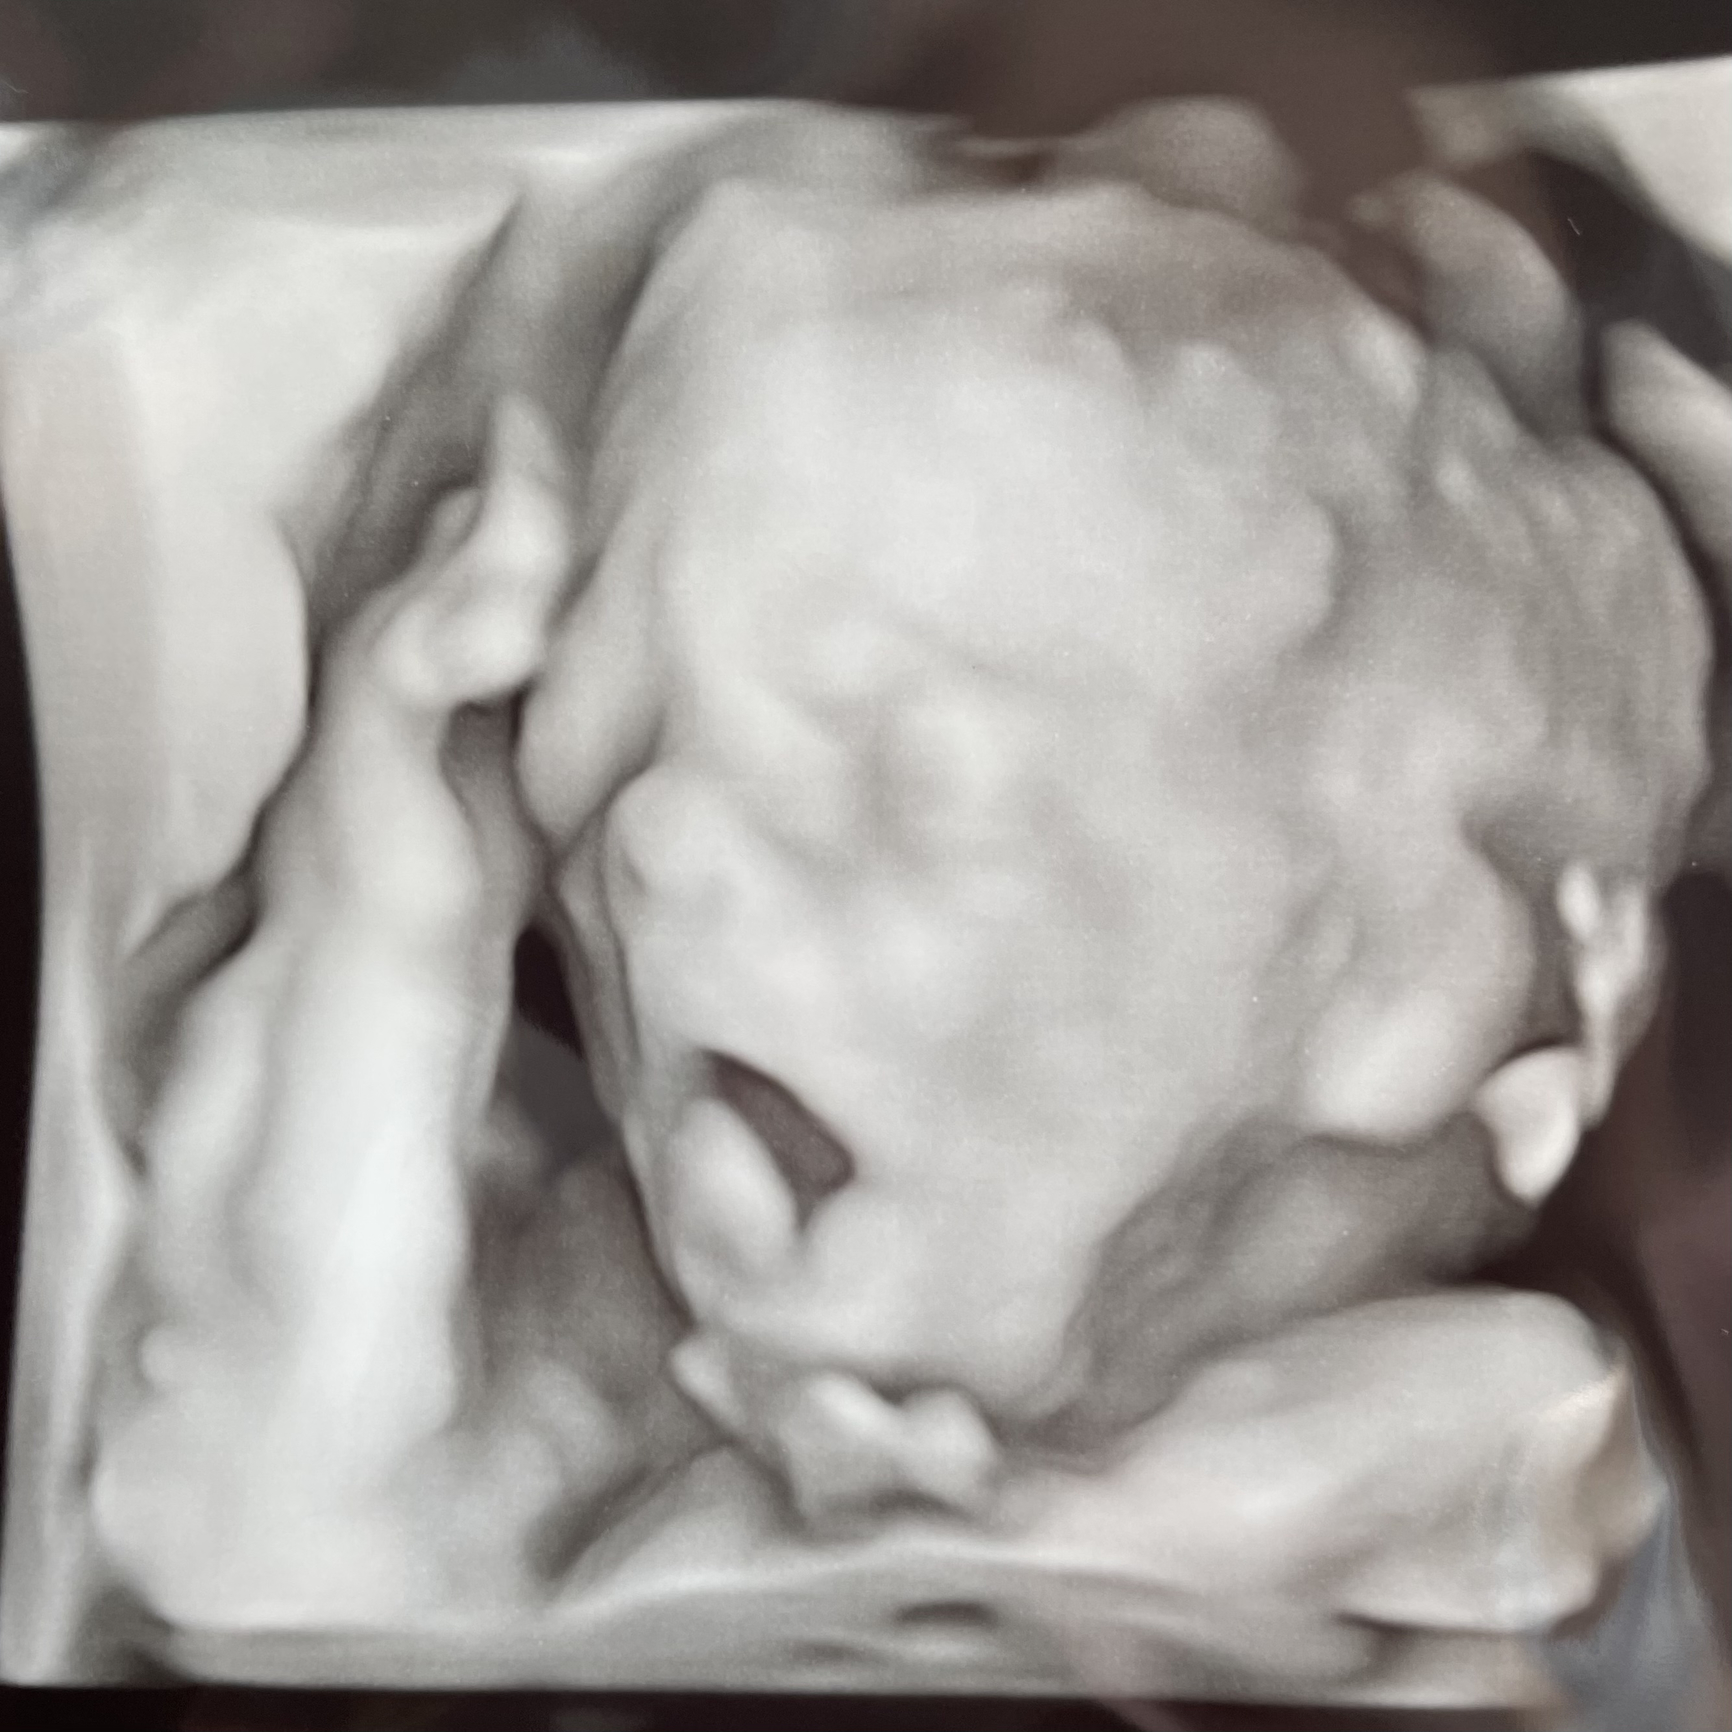

I had my anatomy scan. He is measuring big in the 78th %tile and absolutely perfect. He was moving so much she struggled to get some measurements. She got some incredible 3D pictures of him. Look at that sweet face! 😍